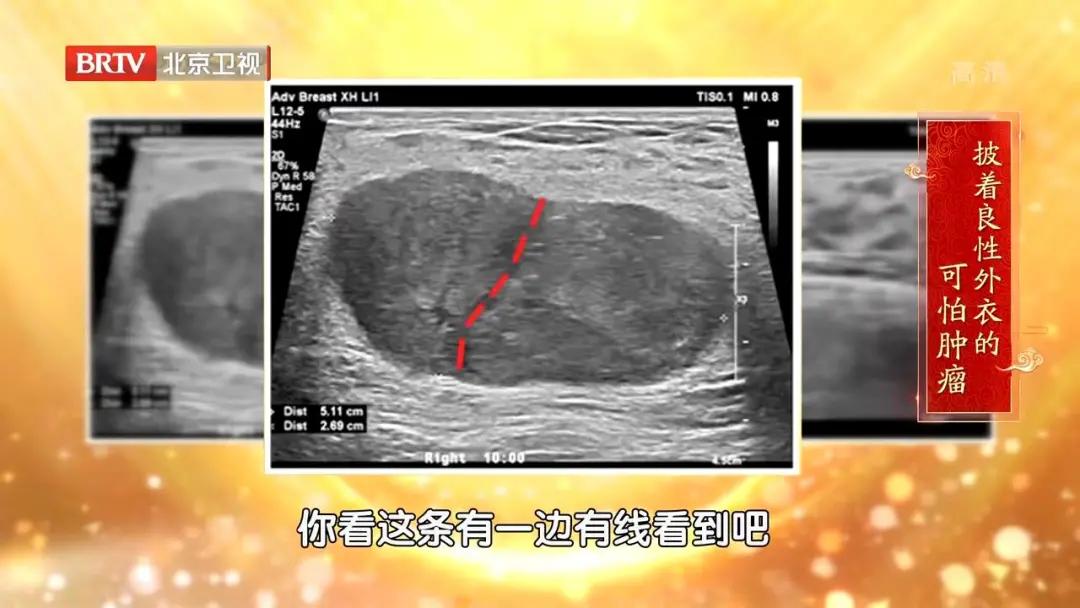

分叶状肿瘤的超声图↑

02 易忽视: 肿物的样子和良性结节非常相似,很多医生都会将它忽视。

超声: 可以直接看到乳房肿块的表现,如有没有包膜、血供,边界是否清楚,是筛查的标准手段。